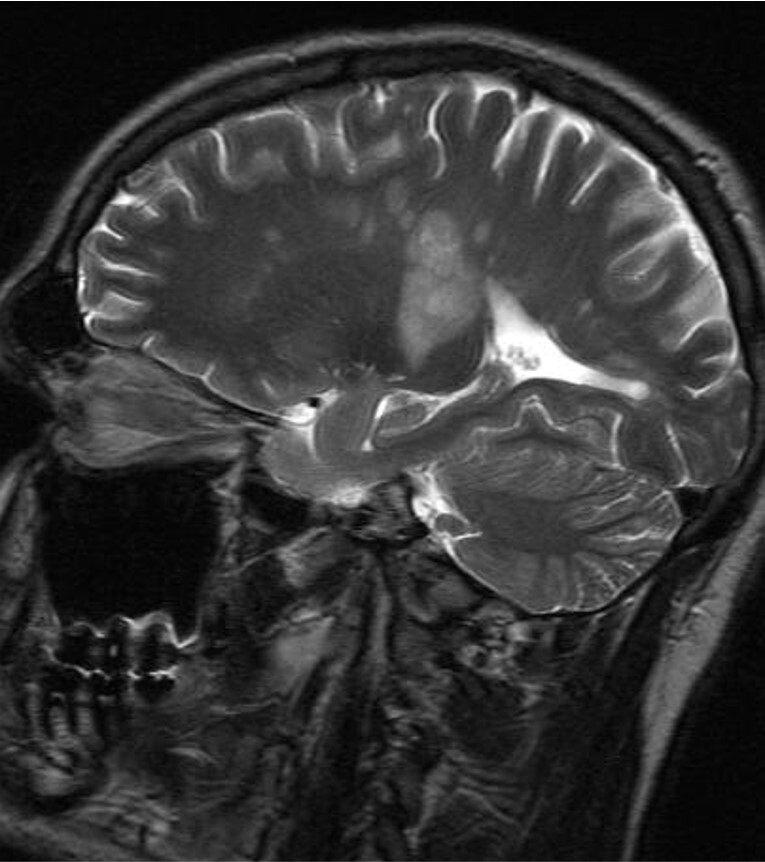

Информация о диссеминированном рассеянном энцефаломиелите